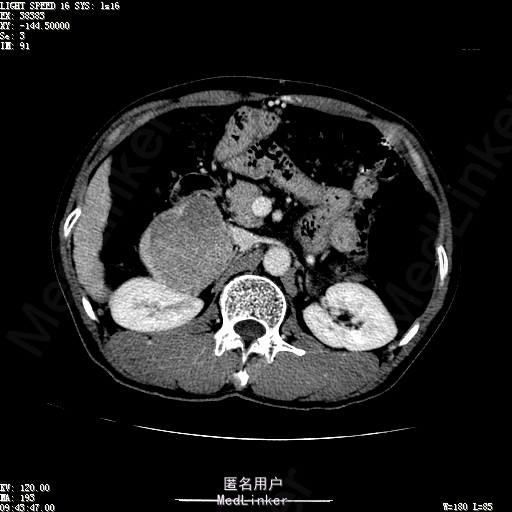

查体:体温36.4℃,脉搏76次/分,呼吸18次/分,血压110/70mmHg。神志清晰,发育正常,营养中等,体位自如,表情安静,慢性病容,检查合作。皮肤粘膜颜色正常,无瘀点、紫癜,有肝掌,无蜘蛛痣,无水肿,毛发的生长与分布正常。浅表淋巴结浅表淋巴结未触及肿大。无巩膜黄染,结膜正常。口唇红润,粘膜正常,舌正常,牙龈正常,扁桃体无肿大,无咽部充血。颈部外形对称,颈静脉正常,肝颈静脉回流征阴性,气管居中。甲状腺正常,无颈部血管杂音。胸部形态正常,呼吸运动平稳规律,无呼吸困难,肋间隙正常。触诊语颤正常,无胸膜摩擦感,肺下界位于右锁骨中线第六肋间。呼吸音正常,未闻及干湿啰音,无胸膜摩擦音。无心前区隆起,心尖搏动正常,心率:76次/分,心律齐,心音正常,无杂音,无心包摩擦音。无大动脉及周围血管征,无奇脉及交替脉,无水冲脉,无枪击音,腹型对称,无腹壁静脉曲张,未见胃肠型及蠕动波,无瘢痕,脐部正常。无压痛,无反跳痛,无腹肌紧张,无腹部包块。肝未触及,Murphy征阴性,脾未触及,肾未触及,无移动性浊音。无肝区叩击痛,无肾区叩击痛,无脾区叩击痛。肠鸣音正常4次/分,无气过水声。外阴及肛门:未查。四肢正常,关节正常,无下肢水肿,无下肢静脉曲张,无杵状指趾。 辅助检查:彩超:肝表面欠光滑,肝内占位5.2*5厘米 ct如下图

诊断:乙肝肝硬化 代偿期 原发性肝癌。 患者病史明确,目前化验转氨酶轻度升高,说明有活动性肝损伤,白蛋白降低提示肝脏合成代谢功能下降,AFP从一年前至今逐渐升高,提示活性肿瘤细胞增多。CT所见明确诊断肝癌,并有周围卫星灶,应近期行TACE治疗。 处置:DSA下肝动脉造影及TACE 手术简要经过:患者平卧位,术区皮肤消毒,铺手术巾,2%利多卡因局麻后,Seldinger法穿刺右股动脉,入血管鞘,5F猪尾管腹主动脉造影,超滑导丝yidao5F RH管腹腔干、肠系膜上动脉、左肾动脉分别造影,腹腔干造影时,见肝右叶7-8处小结节样肿瘤染色,未见外凸生长较大病灶染色。微导管超选肝右动脉注入三氧化二砷碘油混悬液10毫升,横结肠遮挡部位见较大病灶有伞状碘油沉积。复查造影未在见肿瘤染色,拔出导管和血管鞘,穿刺处压迫止血,加压包扎。术毕。

患者术后8天来,无不适,无发热,无腹痛和腹胀,无恶心呕吐,食欲睡眠好,尿便正常。 查体:神志清,巩膜无黄染,心肺听诊无异常,腹软,无压痛,肝脾肋下未触及,移动性浊音阴性,双下肢无浮肿。 复查化验结果:丙氨酸氨基转移酶 116 U/L、天门冬氨酸氨基转移酶 41 U/L、胆碱酯酶 1995 U/L↓、总蛋白 56.3 g/L、白蛋白 25.9 g/L。白细胞计数 5.8 10^9/L、红细胞计数 3.18 10^12/L、血小板计数 175.0 10^9/L、*血红蛋白 83 g/L、血小板分布宽度 15.7 、血小板压积 0.175 %、*红细胞压积 24.6 %、平均红细胞血红蛋白 26.1 pg、平均红细胞血红蛋白浓度 337.0 g/L、平均红细胞体积 77.5 fL、平均血小板体积 10.0 fL、嗜碱性粒细胞百分比 0.4 %、嗜碱性粒细胞数量 0.02 10^9/L、中性粒细胞百分比 70.4 %、中性粒细胞数量 4.10 10^9/L、嗜酸性粒细百分比 2.1 %、嗜酸性粒细胞数量 0.12 10^9/L、单核细胞百分比 12.2 %、单核细胞计数 0.7 10^9/L、淋巴细胞数量百分比 14.9 %、淋巴细胞计数 0.9 10^9/L。甲胎蛋白 23564.00 ng/mL 患者术后第8天开始行FOLFOX6化疗。CT上可见明显碘油沉积,术后甲胎蛋白下降治疗有效。嘱患者术后必须定期复查